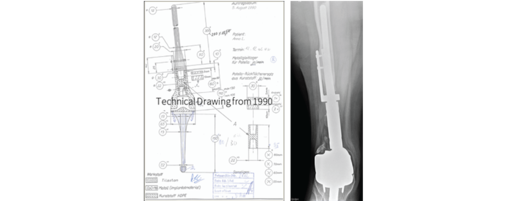

With more than 35,000 individual solutions during the last 50 years. We helped many patients regain their quality of life.